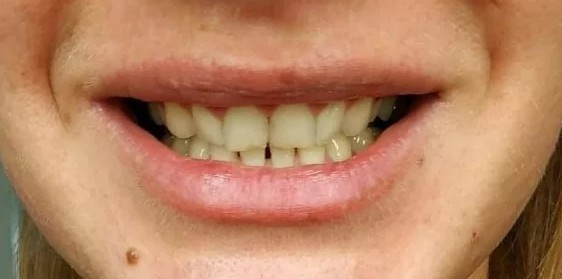

КЛИНИКА ДОКТОРА МУССУРОВА: работы специалистов (92)